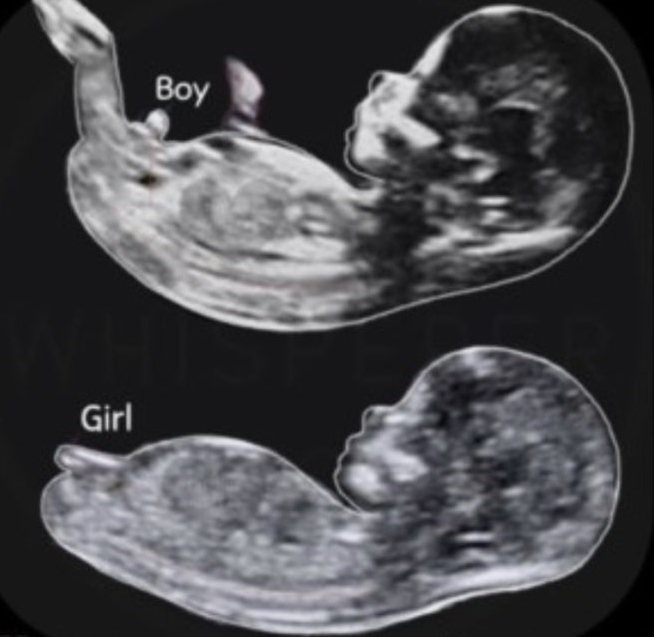

임신 12주부터 초음파 사진을 기반으로 태아의 성기 모양 각도를 분석해서 성별을 유추하는 방법이에요

성기 각도가 30도 이상이면 아들, 이하면 딸인데 저는 아무리 봐도 모르겠더라고요..